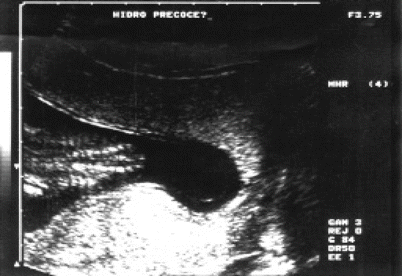

Fig. 4.16

Axial section of the fetal cephalic pole showing the appearance of early hydrocephalus in the context of open spina bifida. Note the choroid plexus (CP) hanging loose, away of the ventricular walls (arrow) very close to the cranial bone plate, with thinning of the brain parenchyma